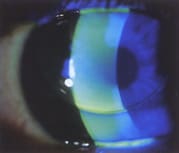

Figure 2. Multifocal aspheric GP lens with inferior positioning. To improve

centration, use a steeper base curve. |

Aspheric progressive designs usually have high eccentricity posterior aspheric and spherical anterior surfaces. A well-centered lens is necessary, and good intermediate visual acuity benefits computer operators (Figure 2).